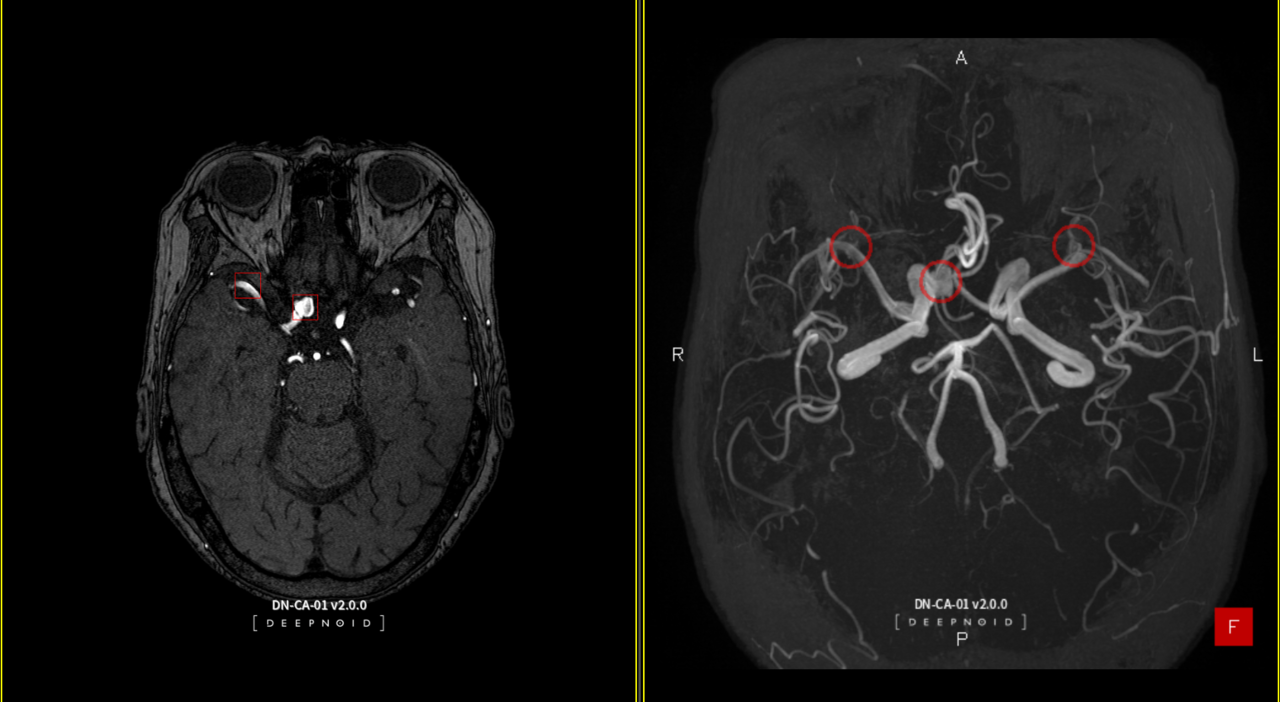

뇌동맥류 진단보조 AI 솔루션 ‘딥뉴로’ 관련 연구는 이번 KCR 2024의 주요 연구에 해당하는 '구연 발표'로 채택됐다. 딥뉴로를 통해 탐지한 뇌동맥류의 위치를 분류 및 측정해 정확성을 평가하는 과정을 담아냈다. 더불어 뇌동맥류 검출 성능 개선에 관한 연구도 구연 발표로 진행한다.

최우식 딥노이드 대표는 "AI 기술력을 기반으로 다수의 연구 성과를 발표, 의료 AI 분야에서 선도적 입지를 다시 한번 확고히 했다"라며 "특히 딥뉴로는 정확도와 성능에서 두드러진 결과를 보여, 실제 임상 적용에 대한 기대가 높다"라고 말했다.